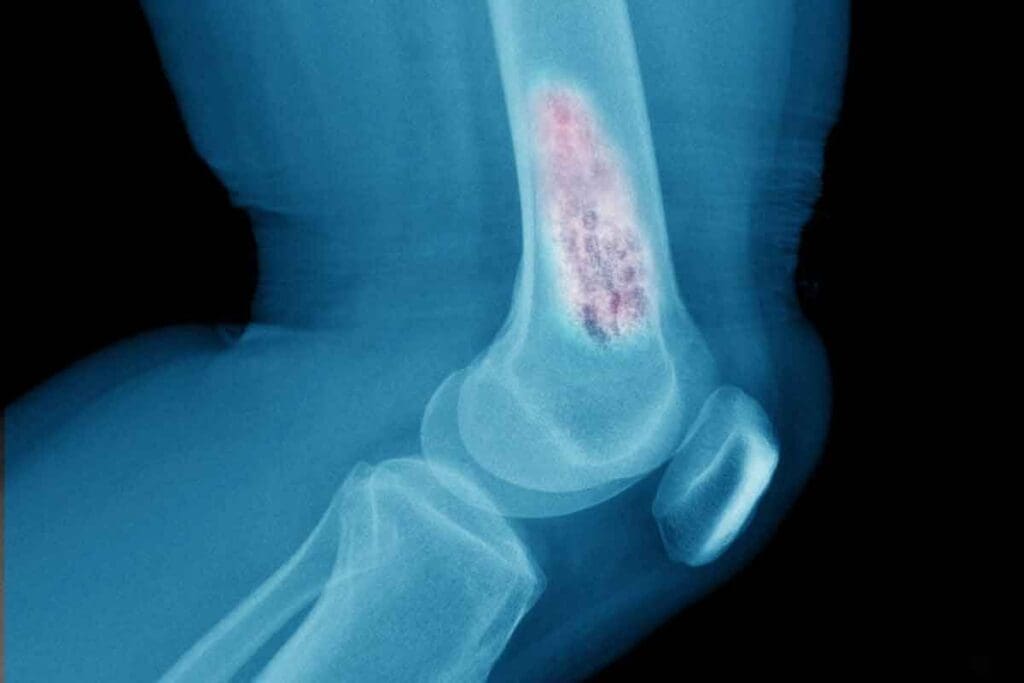

Bone marrow aspiration and biopsy are vital for diagnosing bone marrow cancer. These procedures remove a sample of bone marrow for examination.

Bone marrow aspiration takes out liquid bone marrow. A biopsy removes a small piece of bone tissue. Both give important info about bone marrow cells.

Imaging studies like X-rays, MRI, or PET scans check how far the disease has spread. They also look for bone damage or lesions. These studies help in staging the cancer and planning treatment.

By using blood tests, bone marrow exams, and imaging studies together, doctors can accurately diagnose bone marrow cancer. They can then plan the best treatment for you.